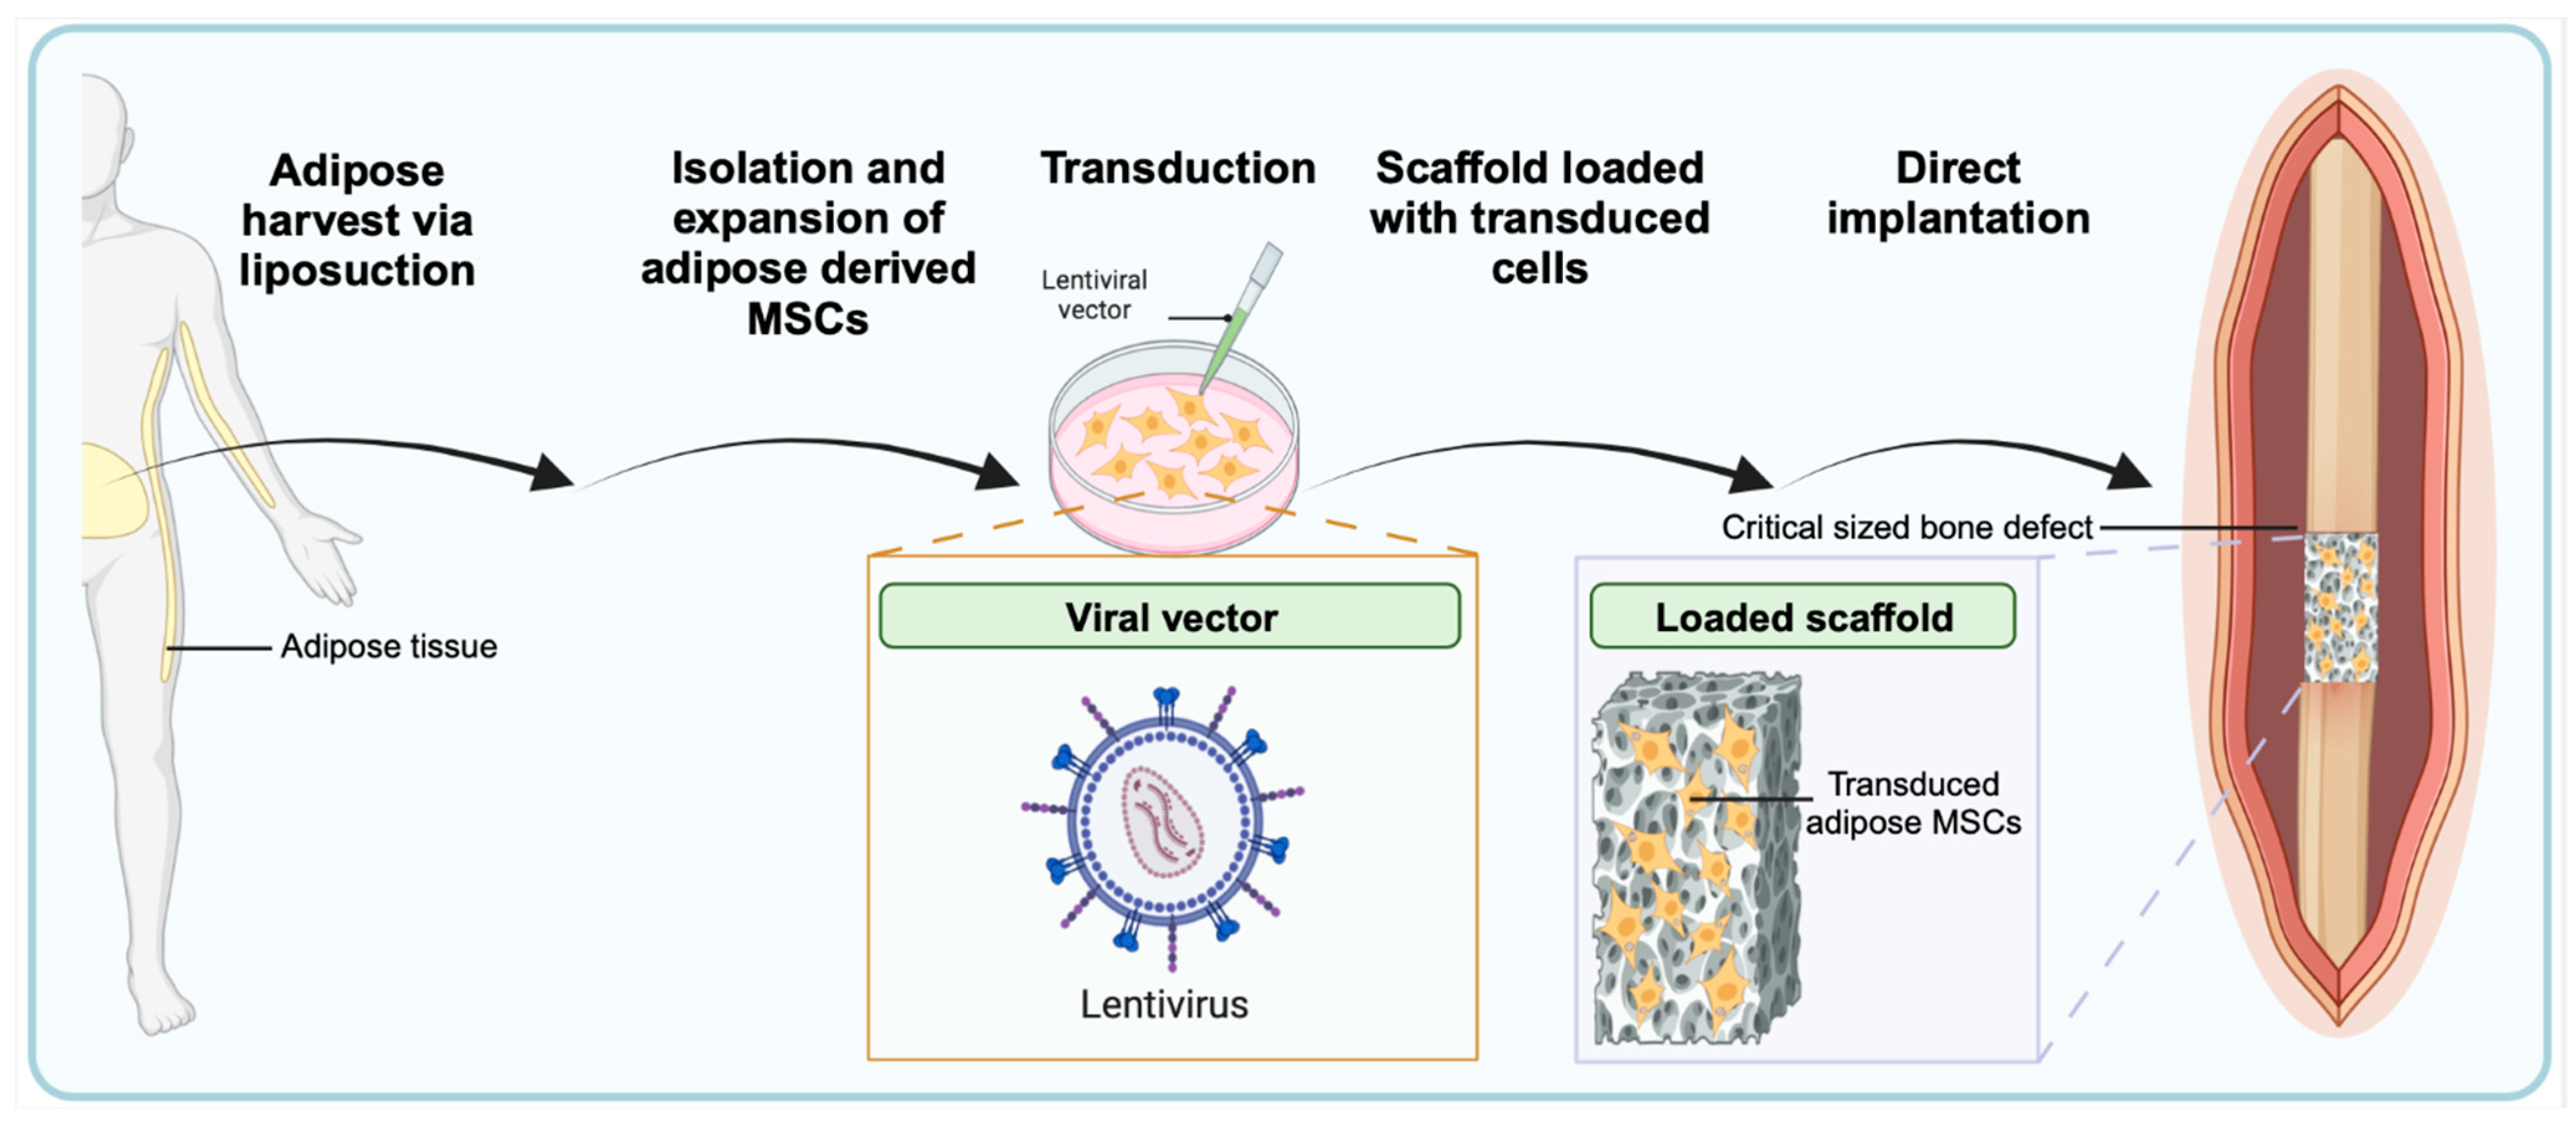

4. Role of Regional Gene Therapy in Growth Factor Delivery

4.1. In Vivo Versus Ex Vivo Regional Gene Therapy

4.2. Viral Vectors

Viral Vector Delivery of Growth Factor in Bone Repair

- Vakhshori, V.; Bougioukli, S.; Sugiyama, O.; Kang, H.P.; Tang, A.H.; Park, S.-H.; Lieberman, J.R. Ex vivo regional gene therapy with human adipose-derived stem cells for bone repair. Bone 2020, 138, 115524. [Google Scholar] [CrossRef]